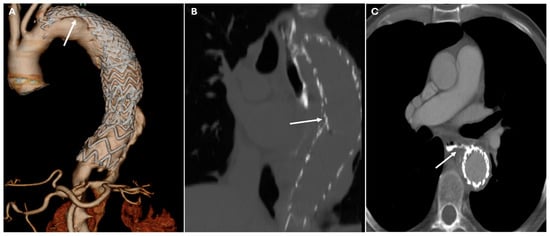

| TEVAR | Descending aortic aneurysms, dissections | Endovascular stent placement | High-density metallic structure conforming to aortic lumen |

| Endoleaks (TEVAR) | Incomplete sealing, graft migration | Persistent contrast enhancement outside stent graft lumen | Can lead to aneurysm expansion and rupture |

| Graft Migration (TEVAR) | Insufficient landing zone, poor fixation | Displacement > 10 mm on sequential imaging | May cause endoleaks or malperfusion |

| Graft Occlusion (TEVAR) | Thrombosis, intimal hyperplasia | Lack of contrast opacification within the graft, collateral vessel formation | May result in ischemia |

| Graft Infection (TEVAR) | Post-surgical infection | Perigraft fluid collections, soft tissue stranding, gas formation, or enhancement of adjacent tissues | Can progress to graft infection and sepsis |